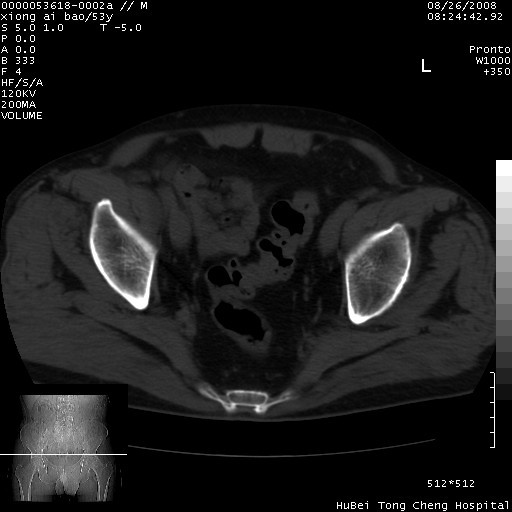

标题: CT15583:M,53Y。请老师指教分析骨盆及其他病变。 [打印本页]

标题: CT15583:M,53Y。请老师指教分析骨盆及其他病变。

股骨头坏死/腹股沟疝。

双侧股骨头无菌坏死,左侧腹股沟斜疝。

非常典型病例,双侧股骨头坏死伴双髋关节周围软组织肿胀,左腹股沟疝。

双侧股骨头坏死伴双髋关节周围软组织肿胀,左腹股沟疝。